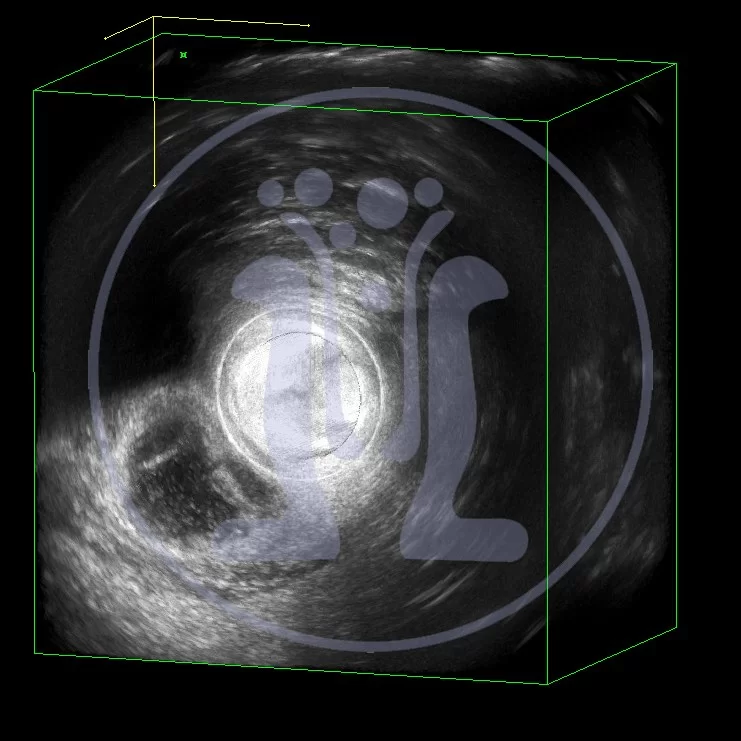

Το πρώτο αφορούσα γυναίκα, η οποία μεγάλο χρονικό διάστημα από διάνοιξη αποστήματος μετά από τοκετό, παρουσίασε σκληρία στην 6η ώρα. Η υπερηχοτομογραφική χαρτογράφηση επιβεβαίωσε την διάγνωση. Εγινε άμεση παροχέτευση του αποστήματος. Η ικανοποιητική παροχέτευση του αποστήματος επιβεβαιώθηκε και υπερηχοτομογραφικά. Η ασθενής είναι σε πολύ καλή κατάσταση.